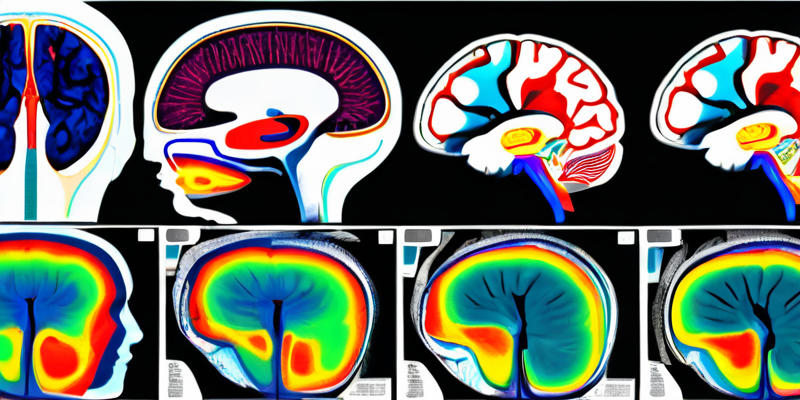

In the realm of medical imaging, particularly in the analysis of brain scans, neural networks have started to revolutionize the way we interpret complex data. One such innovation is the InfiNet architecture for MRI segmentation. This cutting-edge model focuses on the voxel-wise semantic segmentation of infant brain MRI images, enabling more precise analysis and aiding in better healthcare outcomes.

InfiNet is a novel neural network architecture that leverages fully convolutional networks (FCNs) to perform segmentation tasks in medical imaging. Specifically, it is designed to efficiently process infant brain MRI images during a critical stage of development known as the iso-intense stage. The architecture comprises two encoder arms that simultaneously handle T1 and T2 input scans and funnel the data through a joint-decoder arm which culminates in the classification layer.

What makes InfiNet particularly innovative is its approach to upsampling lower resolution input feature maps from these dual encoder arms. Instead of relying on conventional methods, InfiNet uses a process that ties the indices produced in the max-pooling layers of each encoder block to the corresponding decoder block. This allows for non-linear learning-free upsampling, which is a departure from typical upsampling techniques that may add complexity without improving performance.

The performance of InfiNet on infant brain MRI segmentation is particularly noteworthy. The model is trained end-to-end and optimizes for the Generalized Dice Loss, a metric that is highly effective for scenarios with significant class imbalance, such as varying brain tissue types in MRI scans. One of the most impressive statistics of InfiNet is its ability to achieve full-volume segmentation in under 50 seconds. This speed is a marked improvement compared to traditional methods.